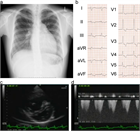

1. PHの定義は、2018年の肺高血圧症ワールドシンポジウムにおいて「mPAP>20 mmHg」とすることが提唱され[1]、2022年に改訂されたERSガイドラインにおいてもこの定義が採択され[2]、世界標準となっている[3](推奨度1)